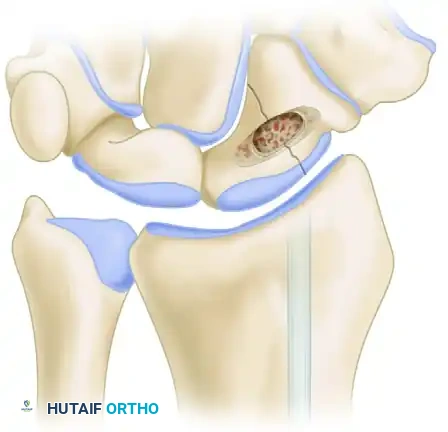

FIGURE 69-37B: The entire proximal row (scaphoid, lunate, and triquetrum) has been completely excised, leaving a void for the capitate to migrate proximally.

FIGURE 69-37C: After the release of traction, the capitate head is shown smoothly seated within the lunate fossa, establishing the new radiocarpal articulation.